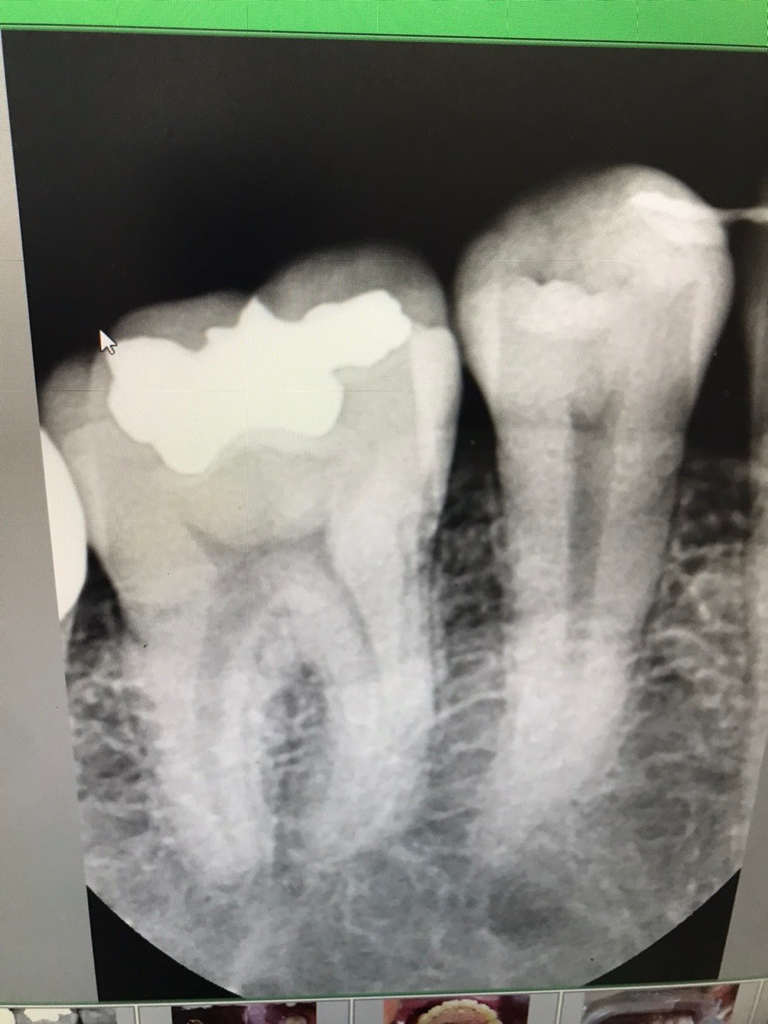

교정후 5번치아가 강하게 물려서 아픕니다

앞니 교정 진행중인데 앞니가 안물려서

5번치아가 강하게 물리고

잇몸살이 살짝 내려갔고 그쪽부분잇몸이 붓고

음식물이 잘낍니다

그래서 치근단 사진을 찍었는데

• 1번 째 사진

사진에는 그다지 이상은 없어보입니다.

교합이 잘 안맞는다면 교합의 일부조정이 필요할 수 있습니다